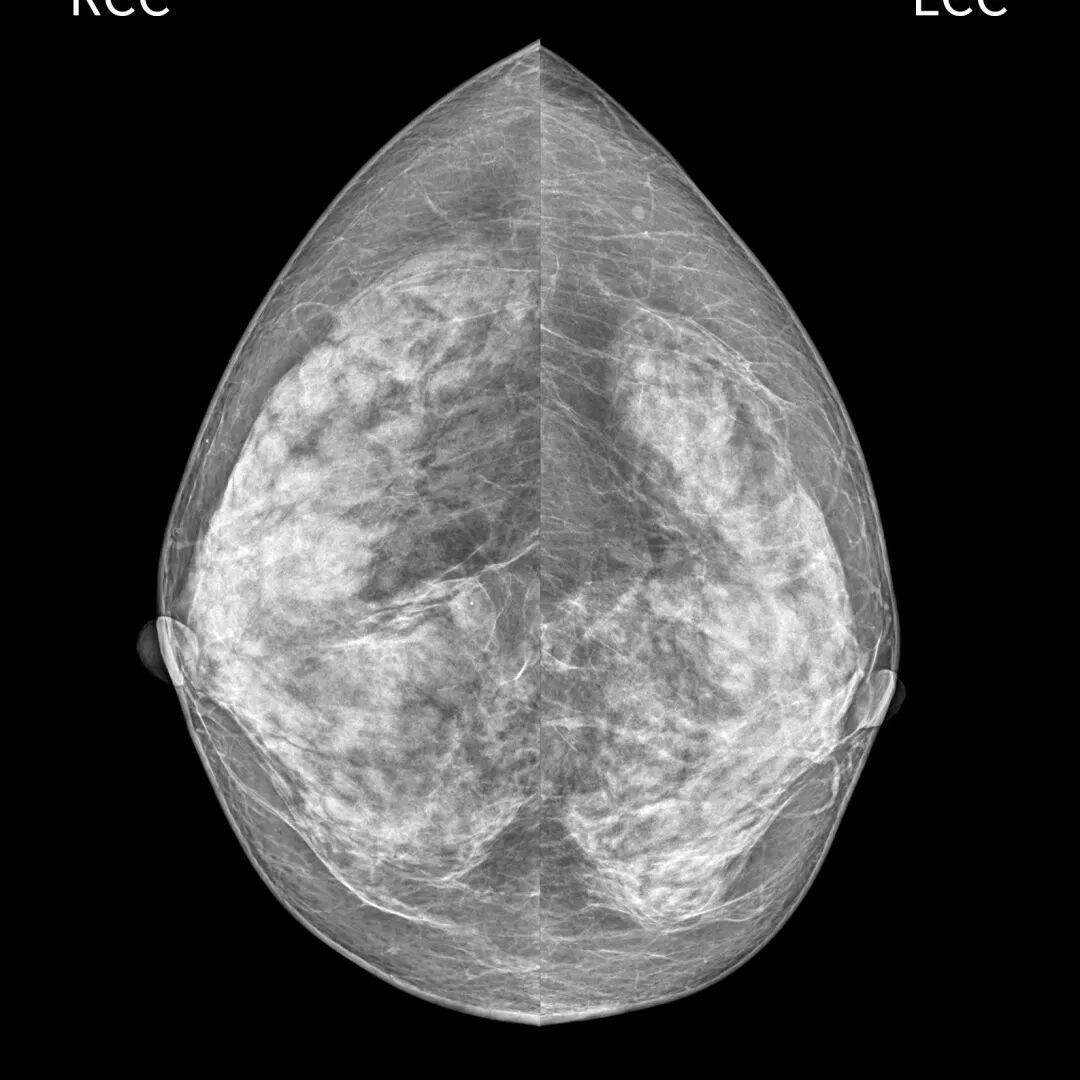

检查样片

深圳蓝影Luna mini全数字化乳腺摄影系统是通过低剂量乳腺X线拍摄乳腺的高端数字乳腺钼靶机。它使用全新大尺寸平板探测器数字成像技术,满足各种尺寸乳腺摄影需求,提高乳腺摄影对低能量X线的吸收率,像素尺寸更小,空间分辨率更高,优质的数字图像让再细微的病变也无所遁形。

该设备能够在乳腺癌的最早期发现病灶,甚至是病灶还处于不典型增生或者原位癌阶段就能诊断发现,能高清晰显示乳房内小于1厘米的结节性病灶,可敏感发现乳腺的微小钙化,清晰“捕捉”早期恶性乳腺肿瘤,并可准确定性、定位,真正做到早期发现、早期诊断、早期治疗的效果,更好地位广大患者服务。